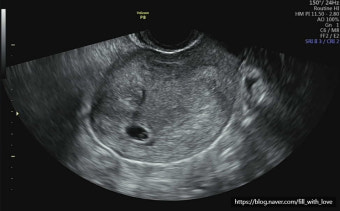

또한, 일부 여성은 너무 초기에 병원을 방문해서 초음파로 태낭이 보이지 않는 경우도 있어요. 이럴 때는 일주일 정도 후에 다시 내원하면 정상적으로 태낭이 보이는 경우가 많습니다. 보통 임신 5~6주차부터 태낭 확인이 가능하므로, 4주차에는 혈액검사만 먼저 받는 것도 좋습니다.